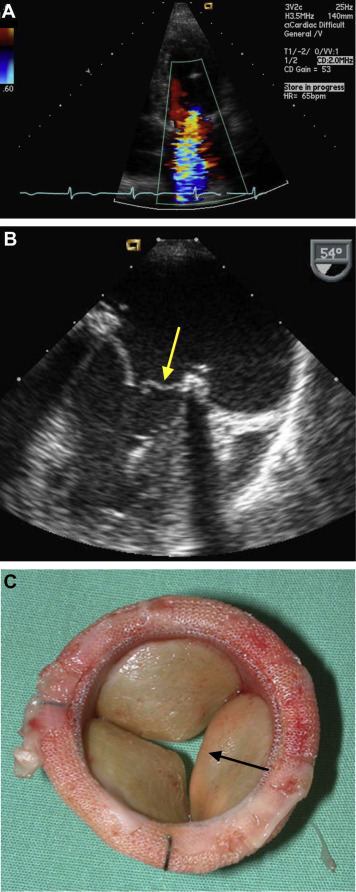

Early Bioprosthetic Valve Failure: Mechanistic Insights via Correlation between Echocardiographic and Operative Findings – Journal of the American Society of Echocardiography